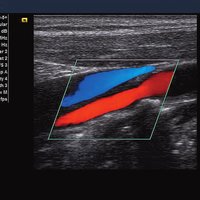

Siemens ACUSON X300 PE Beschreibung

• Features: 3D, 4D, Farb/Doppler